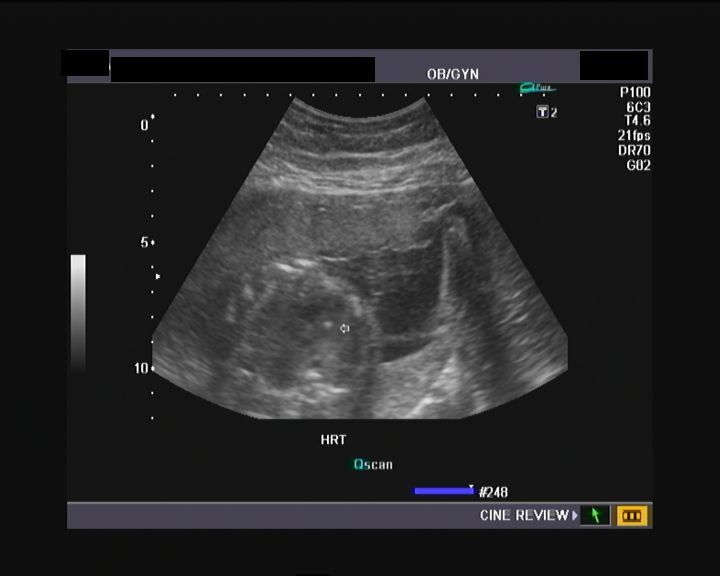

This case study presents a 35-year-old white female who was referred to the UAMS High-Risk Obstetrical Clinic due to advanced maternal age. The patient and her husband received genetic counseling. This was the patient's first pregnancy. She presented with no obvious complications.